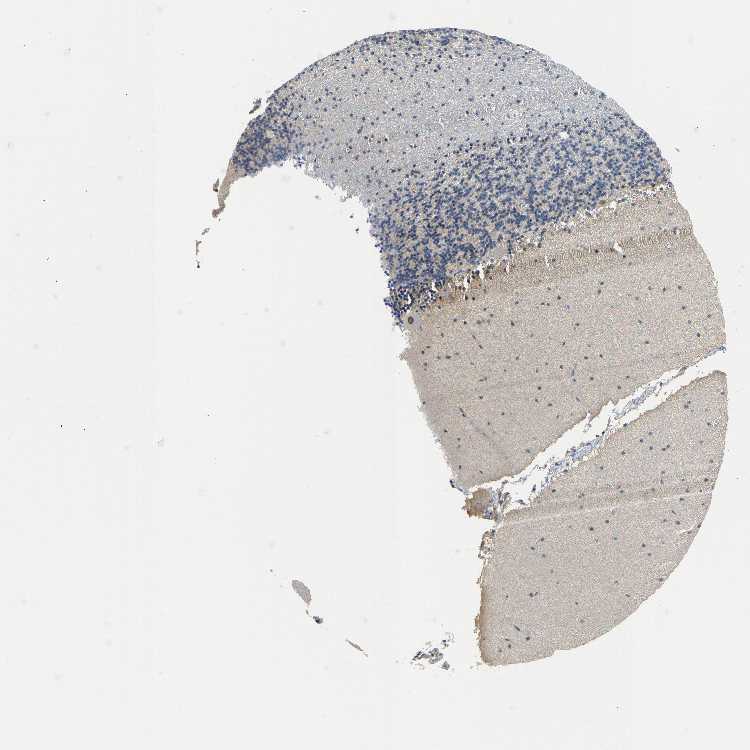

BRAIN CEREBELLUM Show tissue menu

CEREBELLUM - Expression summary

Protein expression

Cerebellumi

On the top, protein expression in current human tissue, based on all annotated cell types, is reported with the units not detected (n), low (l), medium (m) and high (h). Underneath, protein expression in each annotated cell type are reported using the same units.

Protein expression data is based on knowledge-based annotation. For genes where more than one antibody has been used, a collective score is set.

If knowledge-based annotation could not be performed for a gene, no data is displayed here. View antibody staining data further down this page.

h

m

l

n

Cells in granular layer: Not detected

Cells in molecular layer: Low

Purkinje cells: Not detected

CEREBELLUM - Antibody stainingi

Antibody staining in the annotated cell types in the current human tissue is reported as not detected, low, medium, or high, based on conventional immunohistochemistry profiling in selected tissues. This score is based on the combination of the staining intensity and fraction of stained cells.

Each image is clickable and will lead to virtual microscopy that enables deeper exploration of all samples and also displays staining intensity scores, fraction scores and subcellular localization as well as patient and tissue information for each sample.

Antibody HPA018911Antibody CAB025581

Purkinje cells Not detectedMedium

Cells in granular layer Not detectedMedium

Cells in molecular layer LowMedium